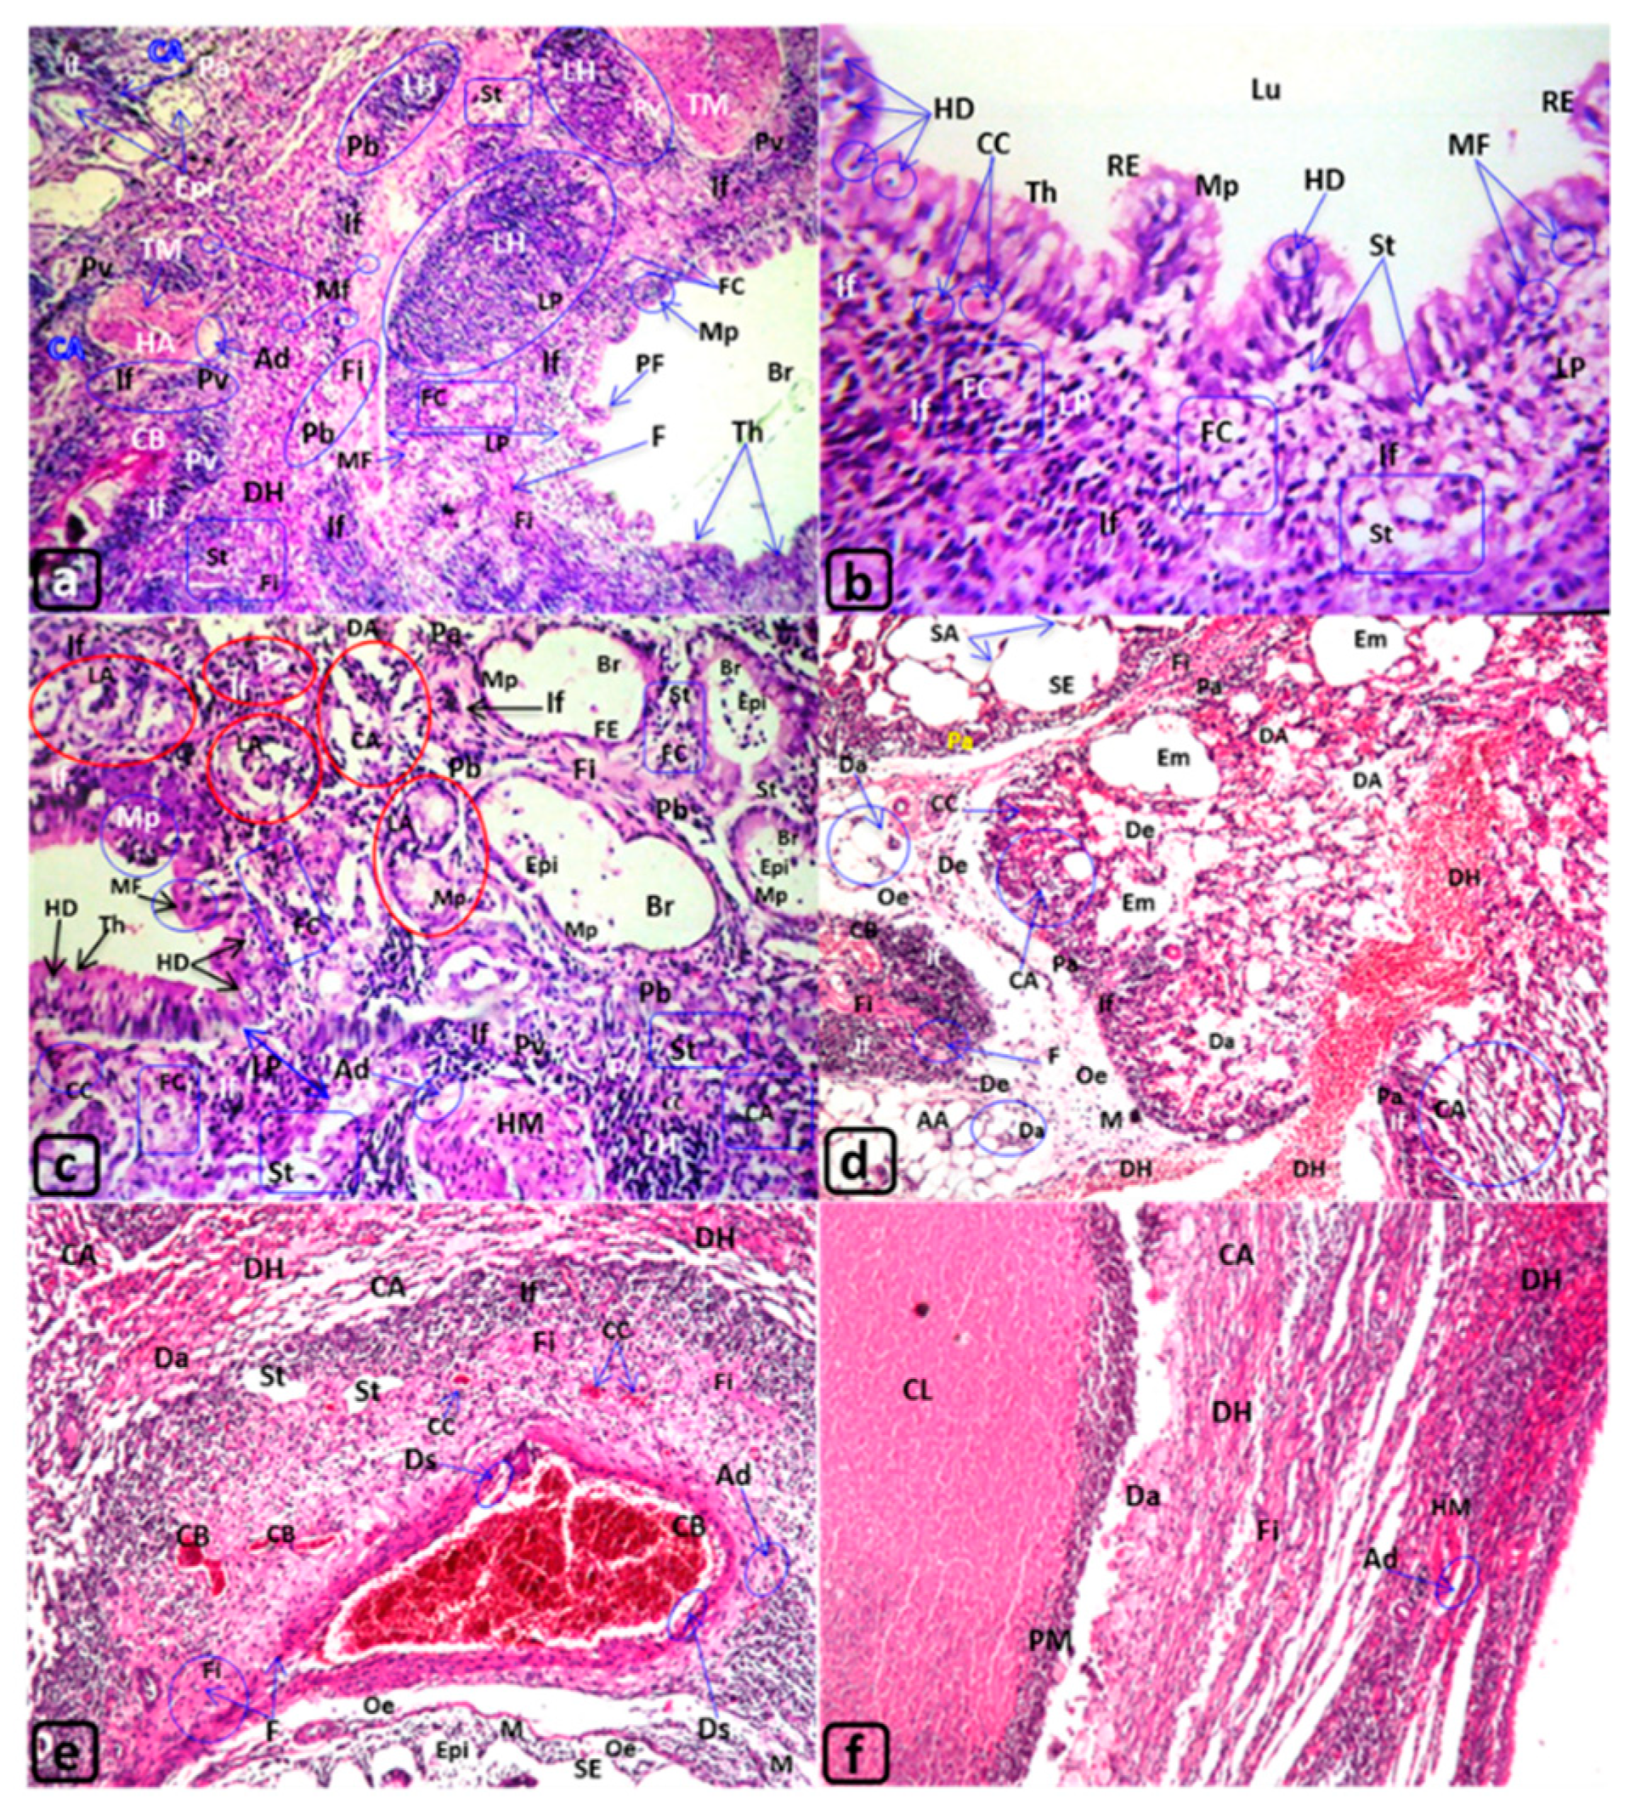

| Trachea of Rats Exposed to MTBE Vapor Inhalation 60 µL/3 min/day for 3, 6, or 12 Months | |||||

|---|---|---|---|---|---|

| Groups | G1 | G2 | G3 | G4 | |

| MTBE exposure | Non exposed | MTBE 60 µL/3 min/day/for 3 months | MTBE 60 µL/3 min/day/for 6 months | MTBE 60 µL/3 min/day/for 12 months | |

| Results | |||||

| Figures | (Figure 1a) | (Figure 1b–d) | (Figure 1e,f) | (Figure 2a–f) | |

| Tracheal lumen “Lu” | Clear | - | - | Epithelialization Epi | |

| Necrotic cells “NC” | |||||

| Mucosal layer: Lining “respiratory “epithelia “RE” | Normal | Ulceration “MUl” | Desquamation “Ds” | ||

| Deciliation “Dc” | Flattened “FE” | ||||

| Polyp formation PF | Degenerative epithelium “DE” | ||||

| --- | Hydropic degeneration “HD” | ||||

| Hyperplasia “Hp” | |||||

| Metaplasia “Mp” | |||||

| Lamina propria “LP” | Normal | --- | Tracheal adenomas “TA” | ||

| Inflammatory cells “IF”, | |||||

| Congested blood vessels “CB”, | |||||

| edema “Oe”, | |||||

| Fibroid changes “Fi” | |||||

| Foam cells “FC” | |||||

| Hyaline cartilage “HC” | Normal | Perichondrial thickening “PeT” | |||

| Deformation “Df” | Increase in diameter “Di” | Di with Degeneration DHC | |||

| Peritracheal connective tissue “CT” | Normal | --- | --- | Foam cells “FC”, fatty degeneration “FD” | |

| --- | --- | Monocytic infiltration “M” | |||

| Edema “Oe” | |||||

| Blood vessels of CT | Normal | Dilated and congested blood vessels “CB” | |||

| Thyroid gland | Normal | ---- | ---- | Degenerated thyroid follicles “DT” | |